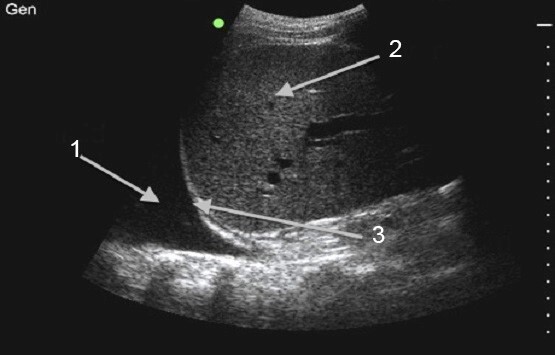

Thoracentesis Lung Image

Fluid

Liver

Diaphragm